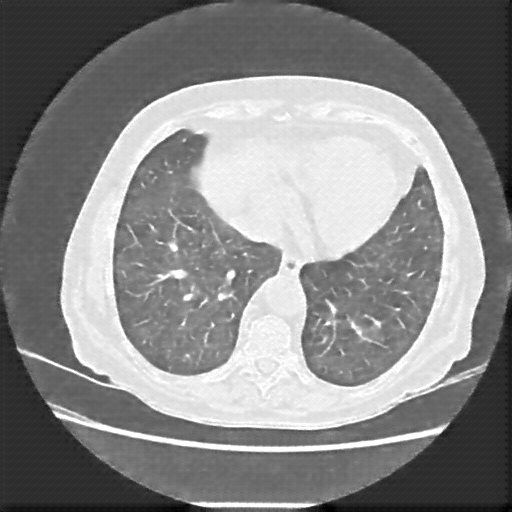

Generated VENOUS CT scan (A→B translation)

Lung window (WL -600, WW 1500 β†’ Low βˆ’1350, High +150)